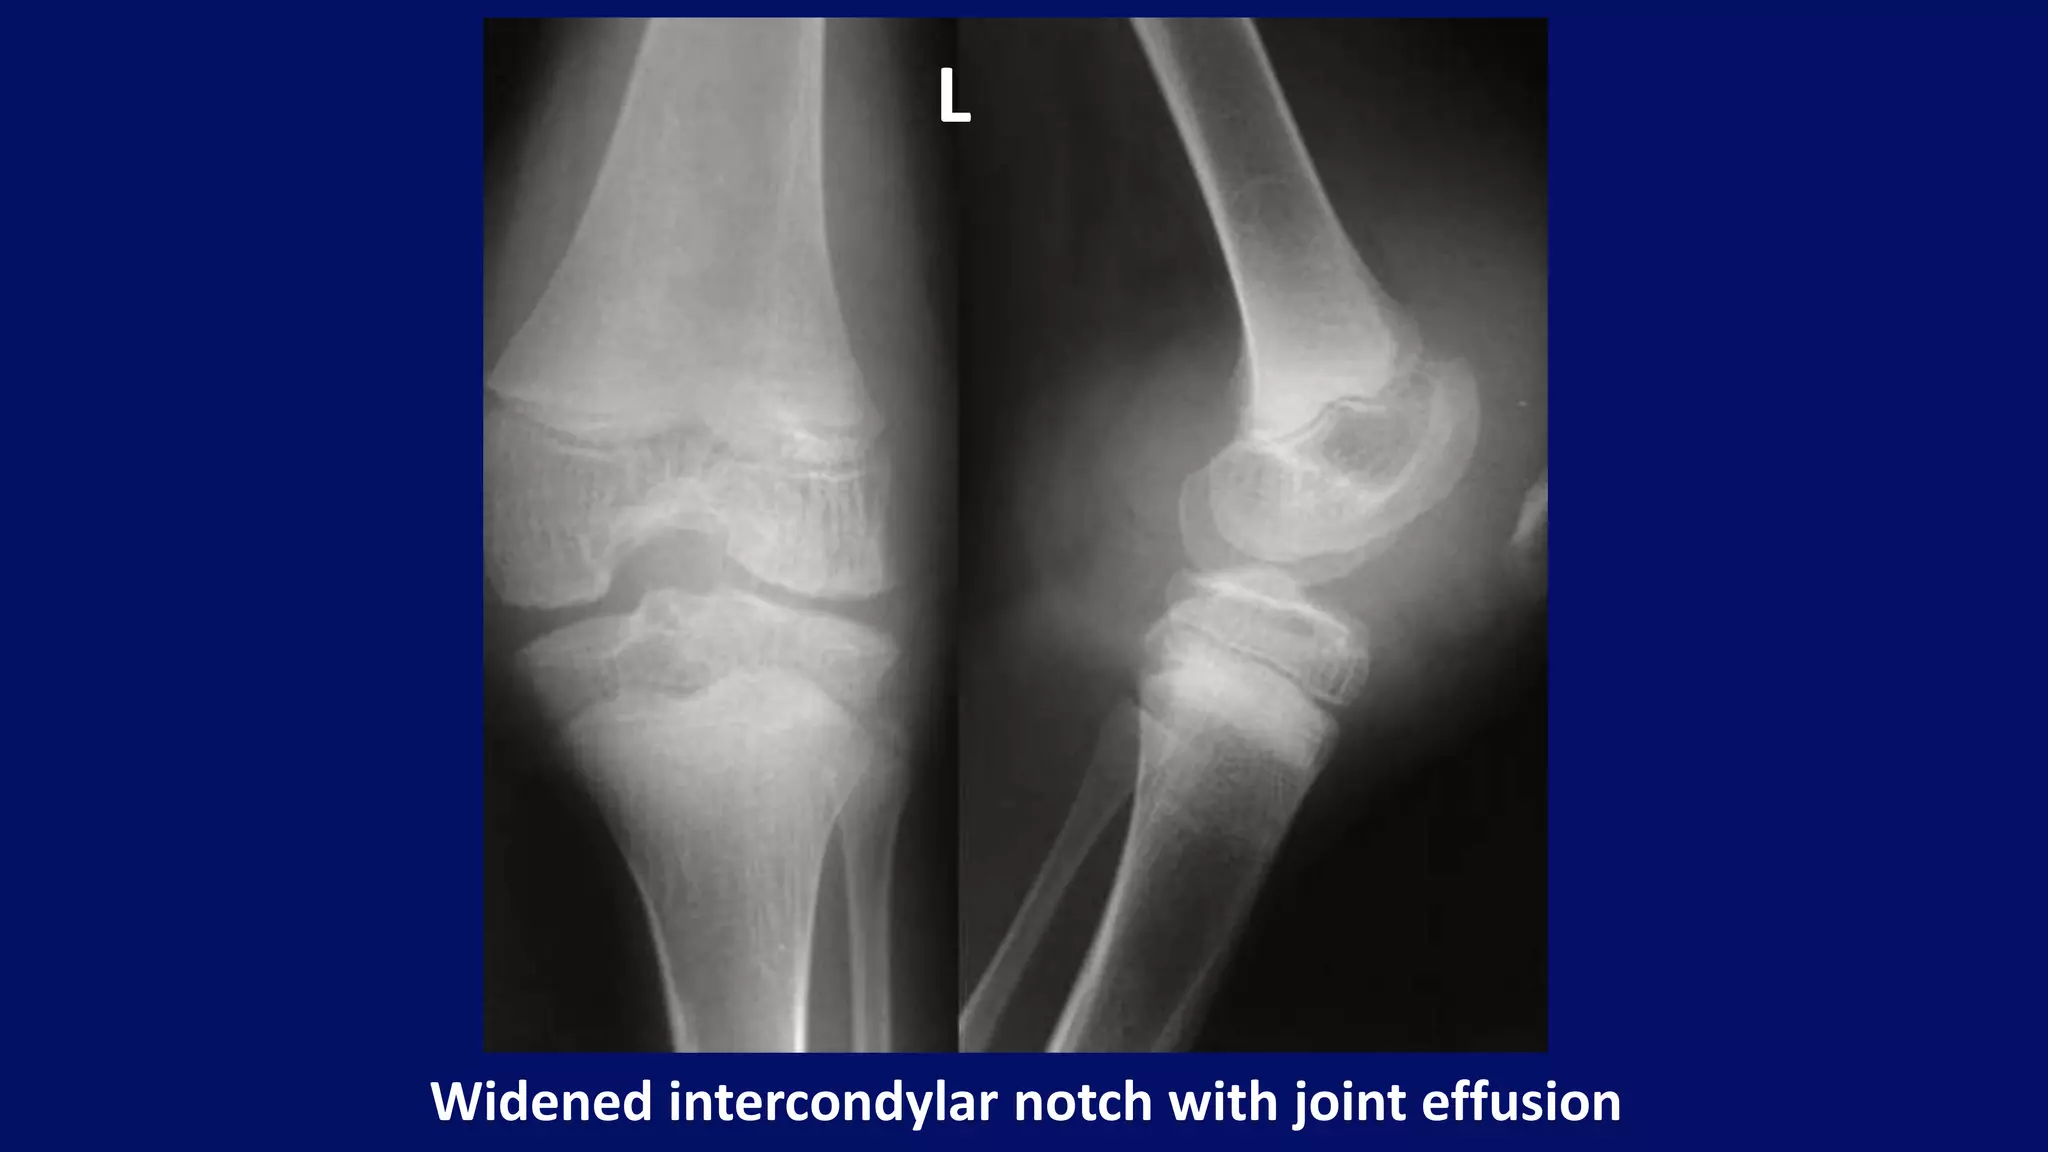

• widened intercondylar femoral notch

Widened intercondylar notch with joint effusion

L

• #118 a soft tissue shadow surrounding the knee joint, s/o joint effusion Periarticular osteoporosis and epiphyseal enlargement are seen at left knee radiograph with widened intercondylar notch. There is also evidence of joint effusion in favour of hemarthrosis.